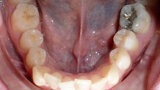

ClearCorrect treatment of crowding